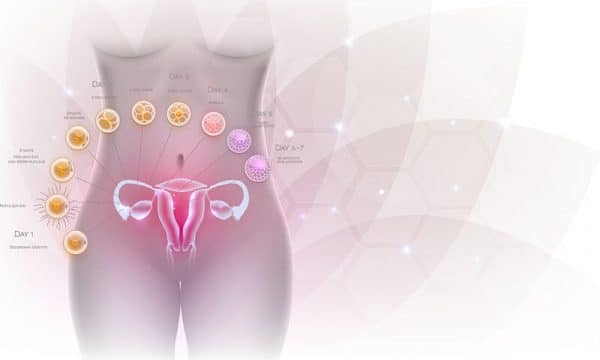

Η ωορρηξία συμβαίνει όταν μία από τις ωοθήκες απελευθερώνει ένα ώριμο ωάριο. Αυτή είναι η στιγμή που το σώμα είναι έτοιμο να λάβει σπέρμα για γονιμοποίηση. Εάν δεν υπάρξει γονιμοποίηση, το αυγό αποσυντίθεται στην επένδυση της μήτρας. Στη συνέχεια, το σώμα θα ρίξει τα υπολείμματα κατά τη μηνιαία περίοδο ενός ατόμου.

Η ωορρηξία διαρκεί οπουδήποτε από 12-24 ώρες. Αφού η ωοθήκη απελευθερώσει ένα ωάριο, επιβιώνει για περίπου 24 ώρες πριν πεθάνει, εκτός εάν το σπέρμα γονιμοποιήσει.

Το σπέρμα επιβιώνει εώς και 5 μέρες

- Εάν ένα άτομο κάνει σεξ ημέρες πριν ή κατά τη διάρκεια της περιόδου ωορρηξίας , υπάρχει μεγάλη πιθανότητα σύλληψης. Αυτό συμβαίνει επειδή το σπέρμα μπορεί να επιβιώσει έως και 5 ημέρες στον τράχηλο. Επομένως, είναι σημαντικό να κατανοήσετε το εύφορο παράθυρο.

- Για να υπολογίσει το παράθυρο γονιμότητας, ένα άτομο πρέπει να σημειώσει την πρώτη ημέρα μιας περιόδου έως ότου εμφανιστεί η επόμενη περίοδος. Αυτό το χρονικό πλαίσιο είναι ο εμμηνορροϊκός κύκλος. Κατά μέσο όρο, οι περισσότεροι άνθρωποι που έχουν εμμηνόρροια έχουν κύκλο 28 ημερών.